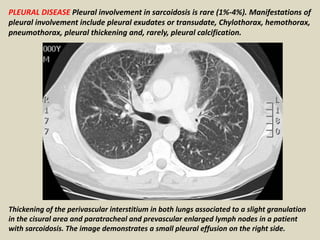

PLEURAL DISEASE Pleural involvement in sarcoidosis is rare (1%-4%). Manifestations of

pleural involvement include pleural exudates or transudate, Chylothorax, hemothorax,

pneumothorax, pleural thickening and, rarely, pleural calcification.

Thickening of the perivascular interstitium in both lungs associated to a slight granulation

in the cisural area and paratracheal and prevascular enlarged lymph nodes in a patient

with sarcoidosis. The image demonstrates a small pleural effusion on the right side.